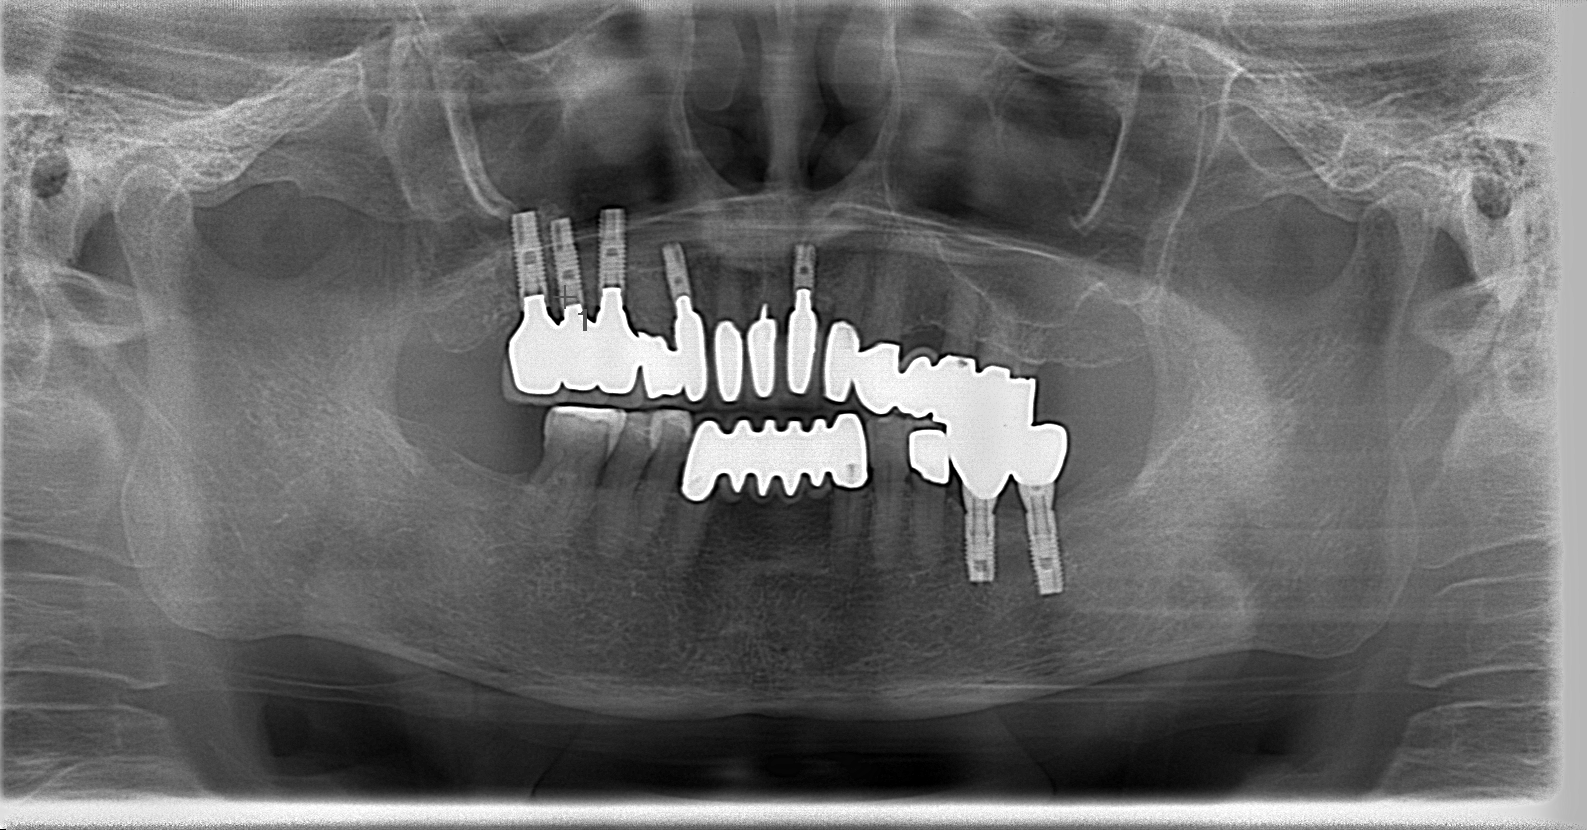

■ 治療内容

右上の骨が少なかったため、まず骨を増やす処置を行いました。

そして、上下にインプラントを入れて「奥歯でしっかり噛める」ように再設計。

治療後は、見た目も自然で、噛む力のバランスも整いました。